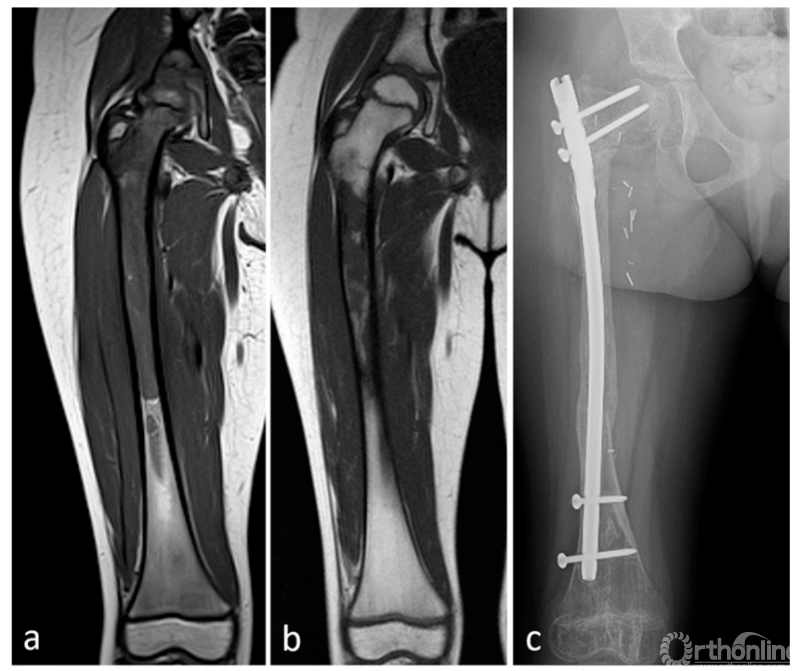

12例化疗前MRI显示骨骺信号异常,其中8例化疗后MRI仍显示异常信号。然而病理学评估显示,8例中只有2例肿瘤发生骨骺累及;其余6例未见骨骺异常。化疗后MRI显示骨骺信号异常的4例中,1例行骨骺保留切除,病理报告为R0切缘。根据化疗前MRI计划的手术切除是不可能保留骨骺的(图2)。在其他3例中,骨骺病理学完全正常。平均随访68个月,组织学边界阴性的患者局部未见复发。

图2 右股骨尤因肉瘤,3岁女童。图2A 化疗前T1加权,显示骨骺信号异常;图2B 化疗后T1加权,显示骨骺信号完全正常化;图2C 术后3年X线片,骨骺保存良好,边缘健康。